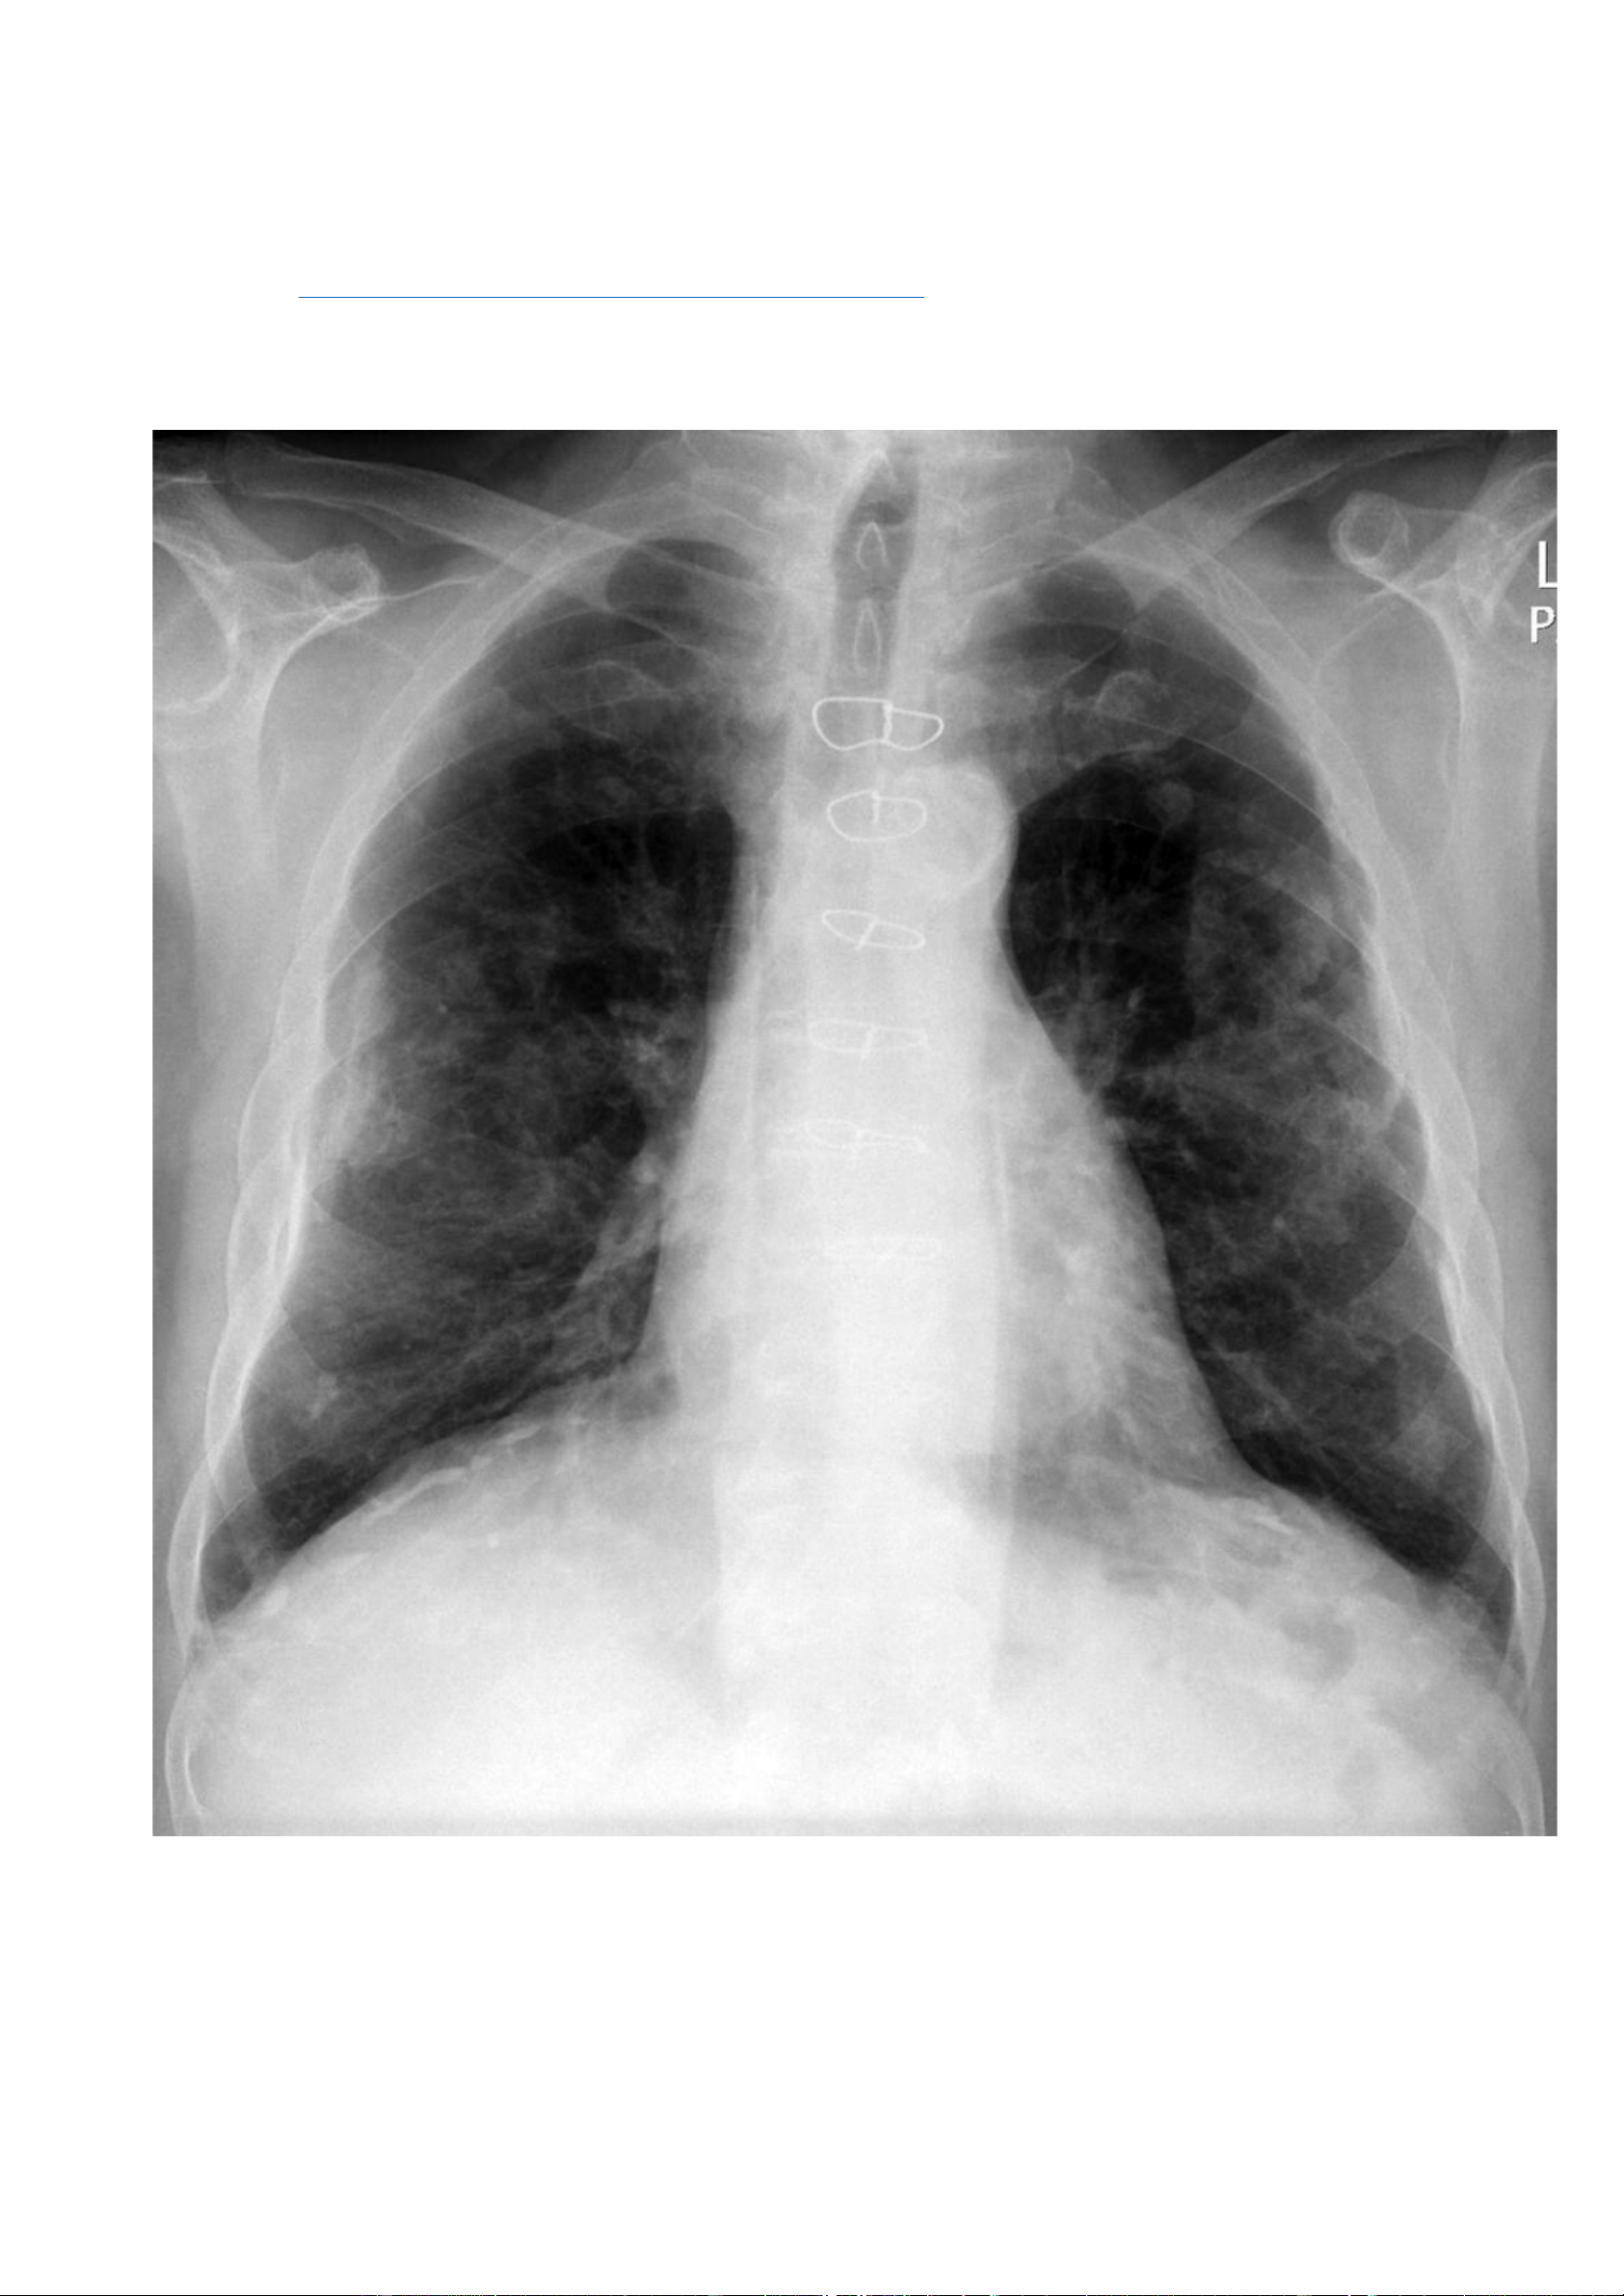

Nguồn link: https://radiopaedia.org/cases/calcified-pleural-plaques - Thông tin bệnh nhân: Không có. - Hình ảnh X quang:

Các hình mờ ranh giới không rõ ở vùng giữa và vùng dưới hai phổi. Vôi hoá dạng đường ở vị trí nửa cơ hoành 2 bên. -